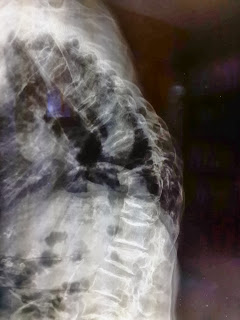

ภาพของผู้ป่วยที่มีหลังโก่งเนื่องจากมีการยุบตัวของกระดูกสันหลัง

นอกจากหลังโก่ง ผู้ป่วยยังมีอาการปวดหลัง ร่วมกับอาการปวดร้าวลงขา ลงน่องและชาบริเวณหลังเท้าร่วมด้วย

ภาพรังสีแสดงการยุบของกระดูกสันหลังหลายระดับ วิธีการดู คือ จะสังเกตจากความสูงของกระดูกสันหลังเทียบกันในแต่ละระดับ จะพบว่าส่วนของกระดูกสันหลังที่ยุบลงนั้นจะมีความสูง

ของกระดูกสันหลังลดลงเมื่อเทียบกับกระดูกสันหลังที่อยู่ติดกัน